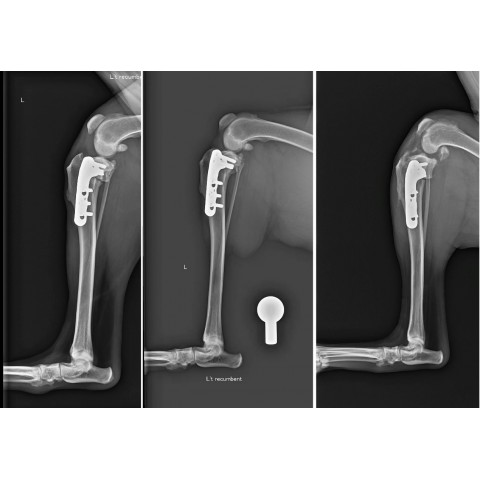

前十字韌帶斷裂手術

後腳跛行的頭號殺手——前十字韌帶斷裂與 TPLO 手術治療 前十字韌帶(CCL)是維持狗狗膝關節穩定最重要的結構,負責防止脛骨向前滑動。不同於人類多因運動傷害造成,狗狗的十字韌帶斷裂通常是長期退化的結果,最後...